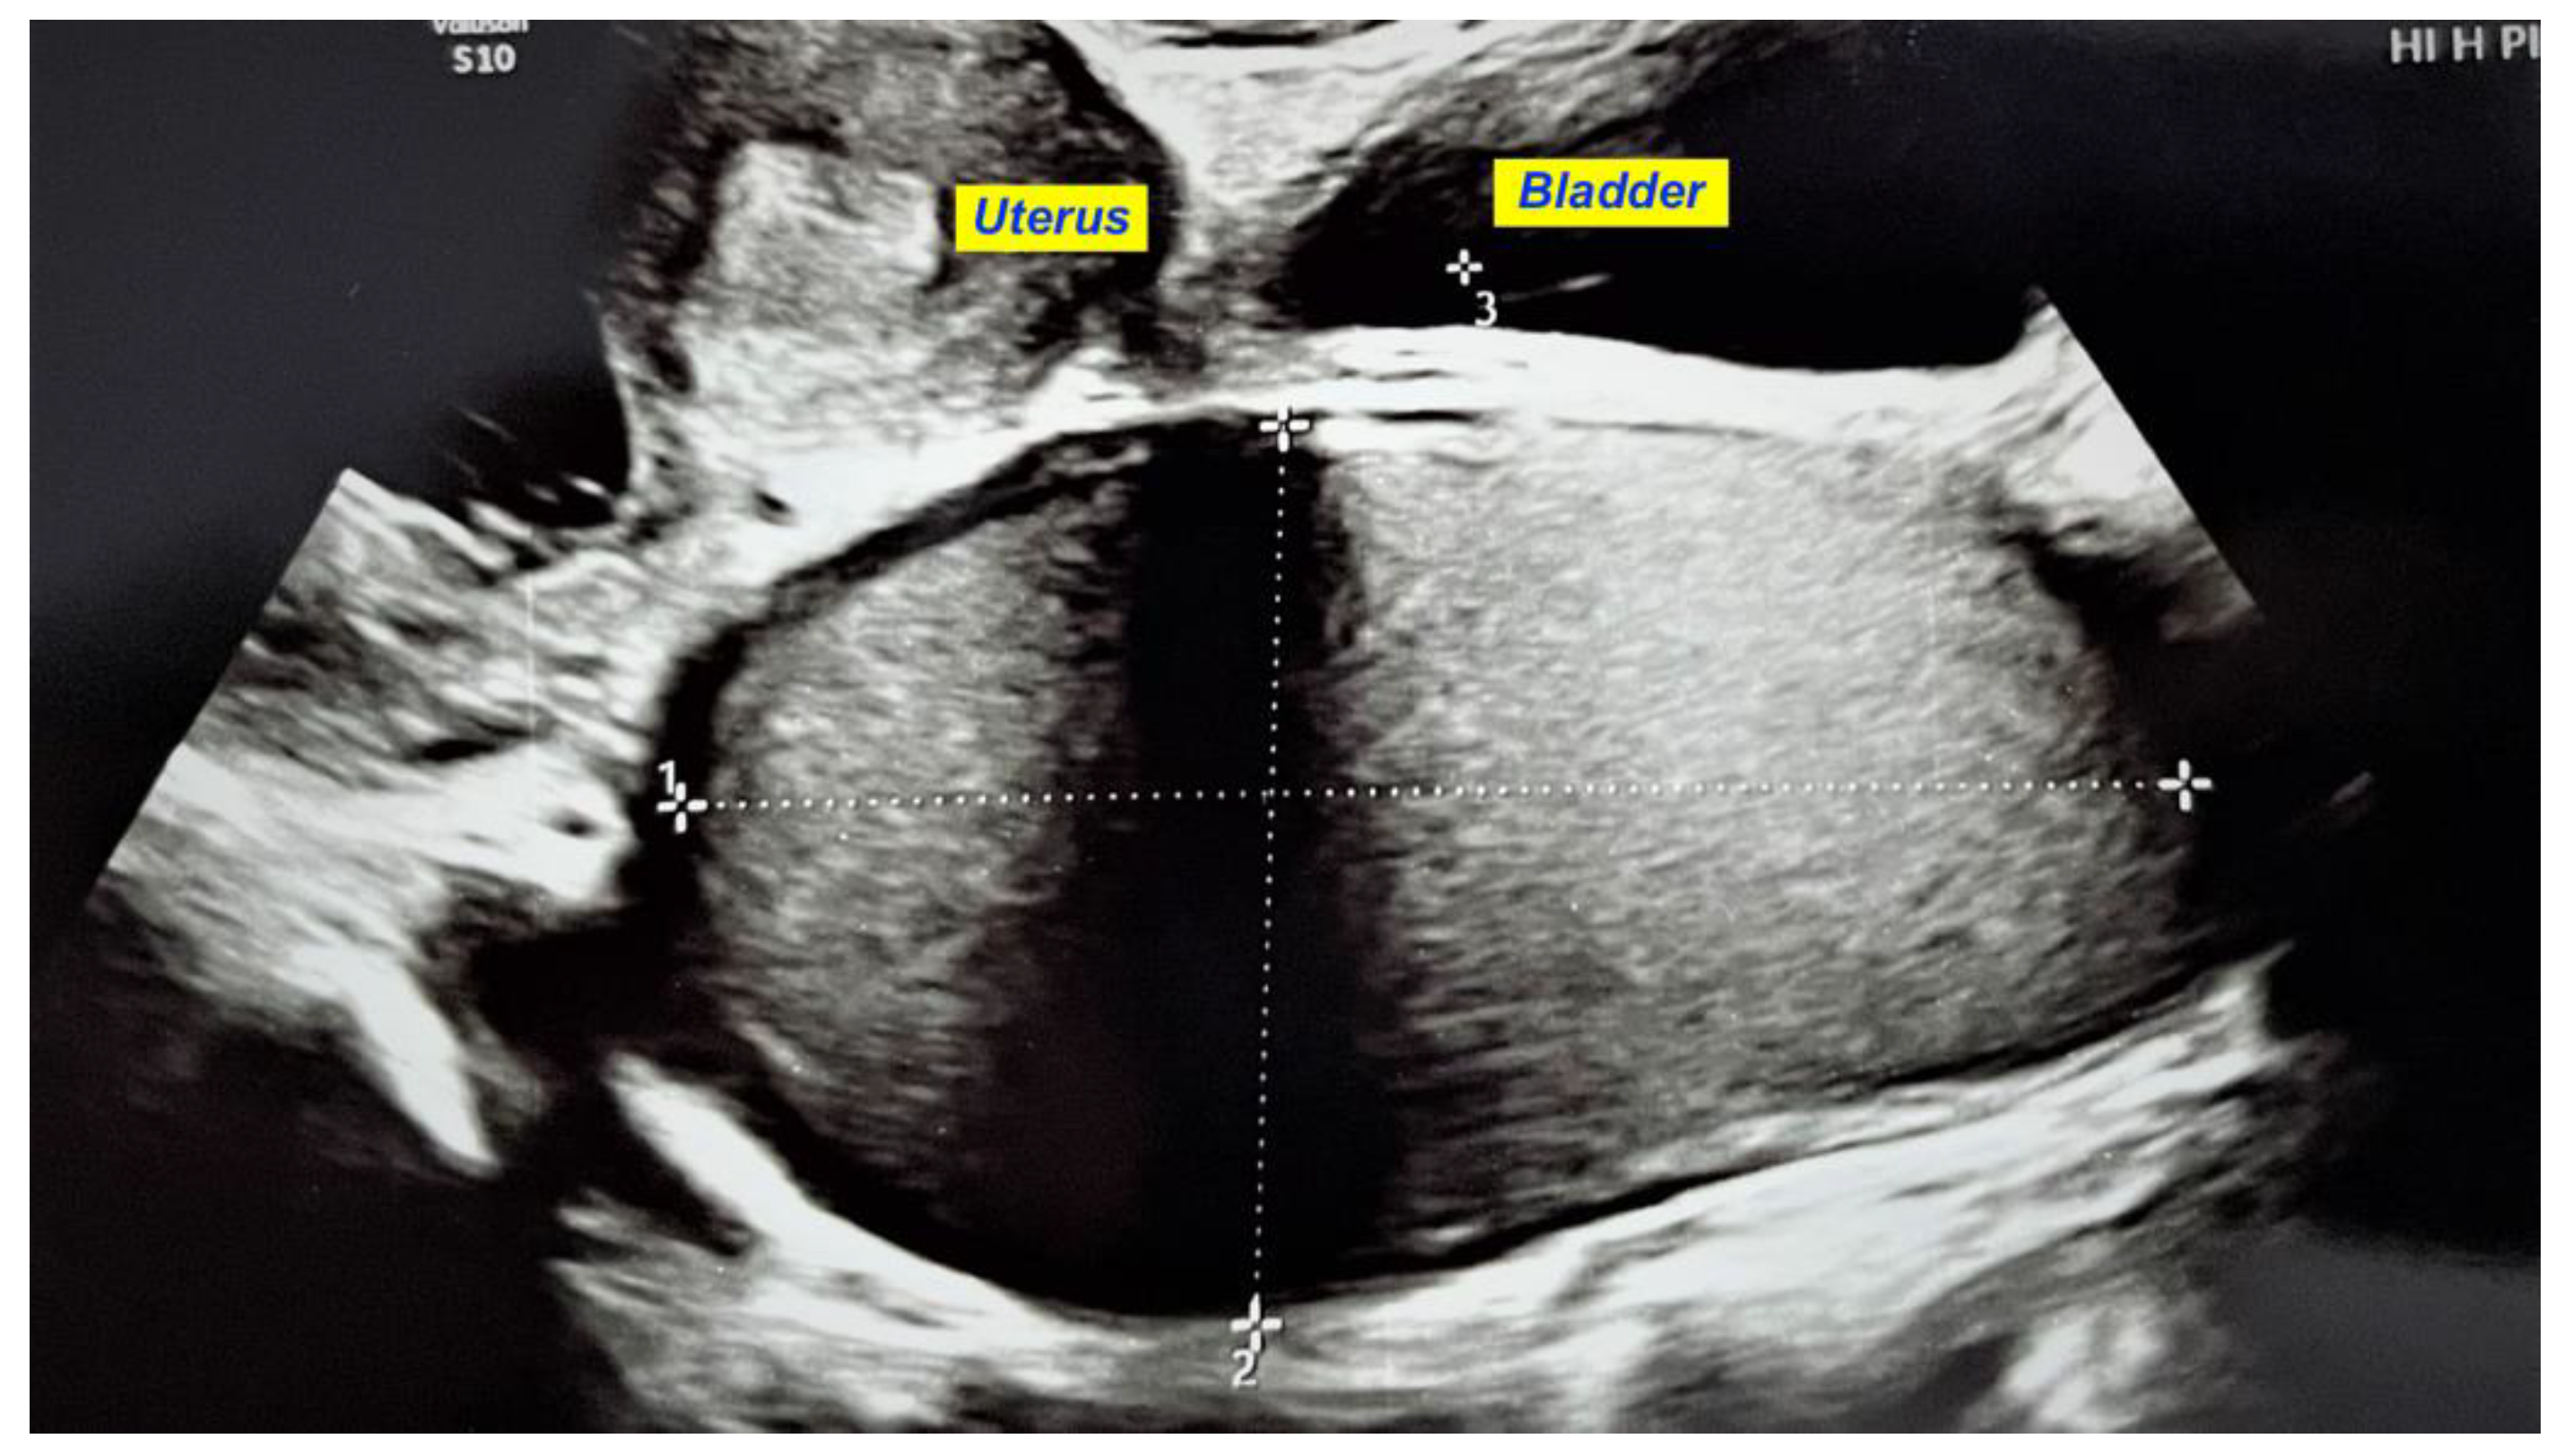

Before starting the vaginal approach, a small hymenotomy was performed to have access into the vagina. The left hemivaginal wall bulged to the midline (a schematic representation of the anomaly and its treatment is presented in Figure 3). Two traction sutures were passed through the vaginal mucosa, above and under the greatest bulging, at a 5 cm distance, and the vaginal wall was incised, followed by the evacuation of 350 mL of a “chocolate-like” content (Figure 4). An adequate excision of the vaginal wall was performed. An 18 gauge Foley catheter inflated with saline was left in the cavity for 24 h in order to facilitate drainage.

Figure 4. “Chocolate-like” (endometriotic fluid) content evacuated after vaginal wall incision.